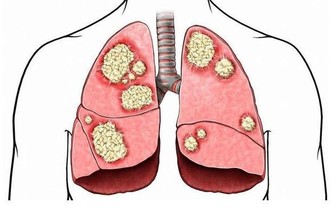

4、肺這個區域適合那些有氣喘或是想讓自己的肺部更健康的人,

雖然按摩可以得到抒緩,

但如果你曾有呼吸困難的狀況,請立刻就醫。